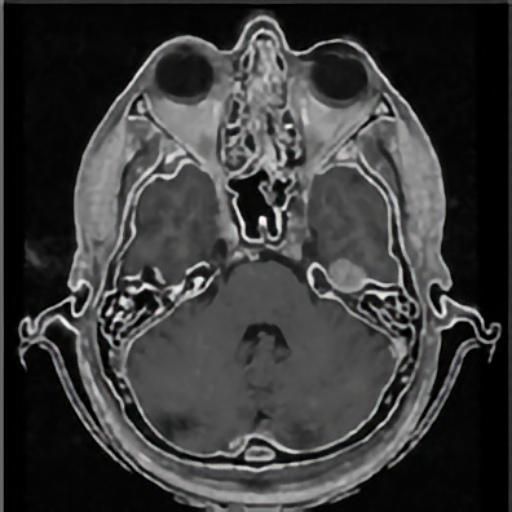

Elastic registration of 2D and 3D multimodal medical images (MR, CT) for diagnosis, surgical planning, and therapy. Spline-based registration approaches using landmarks, intensity information, and landmark localization uncertainties.

Model-based segmentation of vessels from 3D tomographic images. Quantification of the morphology based on 3D parametric intensity models.